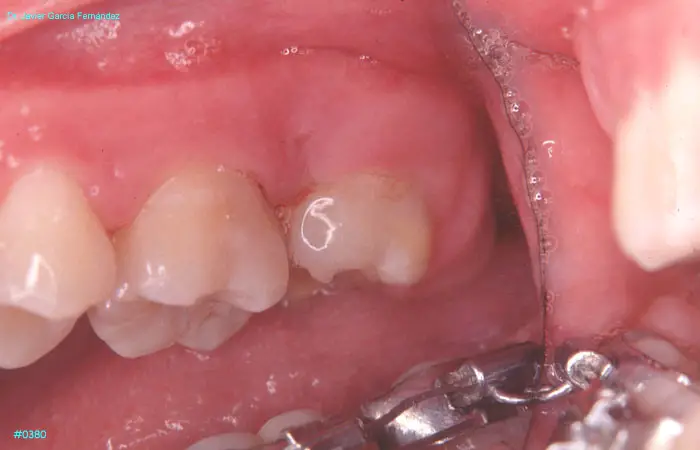

imagen 432